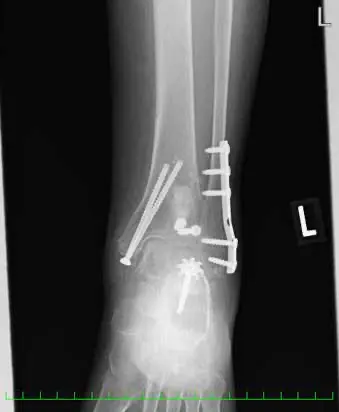

(図1)単純レントゲン像

足関節内外果、脛骨天蓋部に骨折と踵骨アキレス腱付着部より1.5cm近位に骨片を認める。